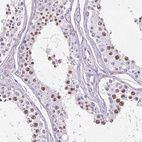

Immunohistochemical staining of human lymph node shows moderate nuclear positivity in germinal center cells.